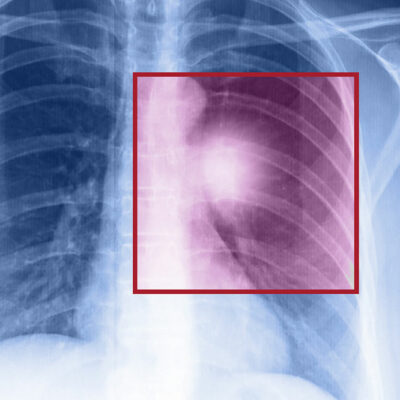

Lung cancer – Types, symptoms, and causes

When the cells in the lungs begin to abnormally multiply and grow, it results in cancer. Lung cancer is one of the leading causes of death in the world. And the risk of suffering from this life-threatening disease is even higher when one is a smoker. Herein, we discuss the various factors that come into play when it comes to lung cancer. Symptoms of lung cancer Usually, lung cancer does not present any symptoms or signs in the early stages. However, as the disease progresses, one may notice Headache Bone pain Loss in weight Hoarse voice Chest pain Shortness of breath Coughing of blood A new cough that persists One should consult a doctor if they notice these signs. If someone is unable to quit smoking, they should visit a medical practitioner for quitting techniques to help avoid this disease. Types of lung cancer There are two kinds of lung cancer: Non-small cell lung cancer This is a catchall term that includes many varieties of this disease, like large cell carcinoma, squamous cell carcinoma, and adenocarcinoma. Small cell lung cancer This happens mainly to people who are heavy smokers, and it’s rarer than non-small cell lung cancer. Risk factors of lung cancer Various factors put you at risk of getting this disease.